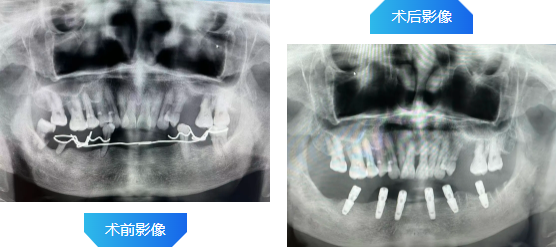

案例一

患者,刘先生,72岁,下牙列缺失多年,曾镶活动义齿不能适应,要求种植修复。